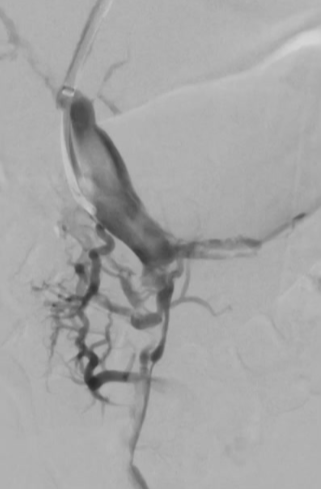

经右侧颈内静脉对肝内门静脉进行穿刺

将 VIATORR CX 型覆膜支架植入体内,以确保能够进入门静脉。 门静脉和肠系膜静脉的血栓清除术 肠系膜静脉中放置带有侧孔的溶栓导管,以处理残留的血栓物质

PVT(门静脉血栓)可能会导致门静脉高压以及侧支循环的形成以及肠道缺血。 抗凝治疗是常规疗法。然而,仅有 39%(6个月内)的患者能够实现门静脉的完全再通。 在血管内治疗技术方面的经验尚显不足,但这类技术确实提供了颇具前景的治疗方案【Pissier 2010】。 TIPS 与血栓切除术及 CDT 结合使用是治疗急性门静脉血栓形成的一种替代疗法,尤其适用于血栓范围广泛的病例。 有必要开展对比不同治疗方法的前瞻性研究,以明确这些方法的益处。 门静脉血栓形成:让“不可能”的经颈静脉肝内门体分流术成为可能……经脾静脉、肠系膜上静脉和肠系膜下静脉 |